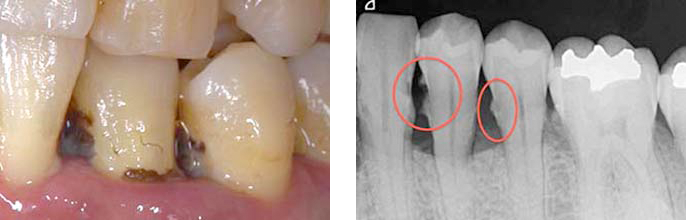

左下:全ての歯に多くの茶色い歯石が付着している、歯石で歯と歯の間が埋まっていることから歯槽骨の喪失も疑われます。

右下:歯石除去をし、歯肉の炎症がとれ引き締まった状態、結果的に治癒とともに歯と歯の間の歯茎の隙間が生じています。

BEFORE(歯周基本治療前)

AFTER(歯周基本治療後)

写真では見えている歯石しか確認できませんが、レントゲンを取ってみると歯肉で見えない部分まで歯石が付いているのがわかります。

BEFORE(歯周基本治療前 レントゲン)

AFTER(歯周基本治療後 レントゲン)